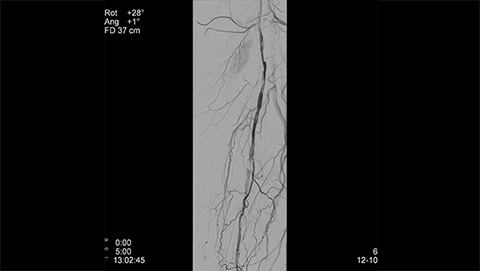

Dynamic 3D Roadmap provides a sustainable 3D roadmap to support interventional procedures. Dynamic 3D Roadmap matches the real-time 2D fluoroscopy images with the 3D-RA reconstruction of the vessel tree. It provides a 3D real-time insight of the advancement of the guide wire, catheter and coils through complex vessel structures. The Unsubtracted 3D Roadmap option reduces subtraction artifacts caused by patient breathing and movements, providing a clear roadmap during abdominal and thoracic interventions.

Live 3D Roadmap allows you to follow the advancement of guidewires, catheters and coils in real-time. It automatically adapts in real-time to changes in C-arm angulation and rotation, table movement, field of view and source-image distance.